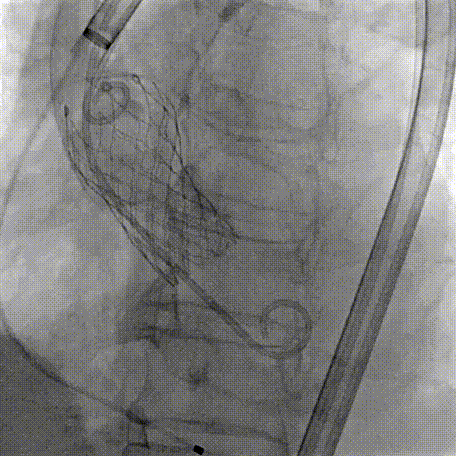

Step 1.升主动脉情况评估

Step 2.建立大鞘通路:大鞘通过升主、边进入边加弯,避免剐蹭弓部斑块

过弓示意图